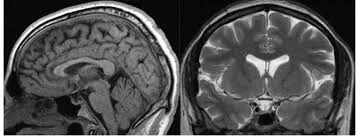

Магнітно-резонансна томографія (МРТ) турецького сідла — це високотехнологічне сканування, яке здійснюється без участі рентгенівських променів. Турецьке сідло — це кісткове ложе, де розташований гіпофіз, який є ключовою ендокринною залозою в організмі людини.

МРТ є незамінним методом для виявлення найменших змін та порушень, пов'язаних із цим органом. Завдяки високій контрастності м'яких тканин, МРТ може діагностувати не лише структурні зміни гіпофіза, але й виявляти ознаки внутрішньочерепної гіпертензії (підвищеного тиску), фіксуючи розширення шлуночків мозку або наявність аномальних порожнин, заповнених рідиною.

Magnetic Resonance Imaging (MRI) of the sella turcica (the bony structure housing the pituitary gland) is a high-tech scanning method performed without X-rays. The pituitary gland is a crucial endocrine organ, and MRI is the indispensable tool for detecting the slightest changes or disorders related to it.

MRI's superior soft tissue contrast allows it to detect not only structural changes but also signs of intracranial hypertension (increased pressure), visualizing enlarged cerebral ventricles or fluid-filled cavities.